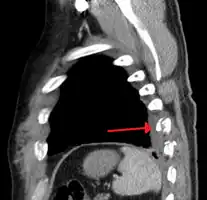

Plain X-rays often pick up displaced fractures but often miss undisplaced fractures.[13] CT scanning is generally able to pick up both types of fractures.[13]